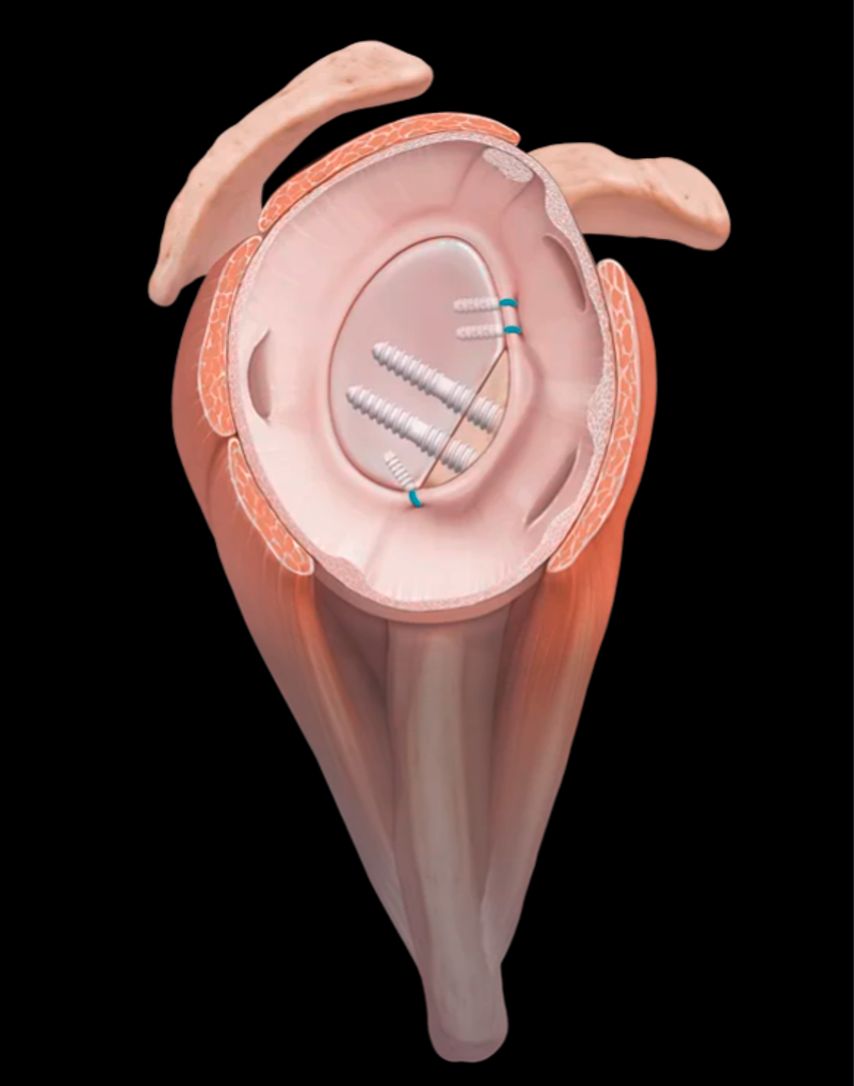

Zur definitiven Fixation stehen unterschiedliche Techniken zur Verfügung. Die arthroskopisch assistierte Schraubenosteosynthese wird meistens durch das 5-Uhr-Portal durchgeführt. Kanülierte Schrauben (2,7–3,5mm) bieten, insbesondere bei größeren, kompakten Fragmenten, eine hohe Primärstabilität, ihr Einsatz ist jedoch technisch anspruchsvoll und mit dem Risiko einer intraartikulären Implantatprominenz verbunden. In den letzten Jahren sind aber Systeme mit bioresorbierbaren Implantaten hinzugekommen, die für die vordere Glenoidaugmentation entwickelt wurden (Abb. 5). Dieses System eignet sich auch perfekt für die Fixation des Glenoidfragments.

Alternativ kann bei knöchernen Bankart-Läsionen eine Fadenankerrefixation durchgeführt werden. Dabei werden Fadenanker medial der Fraktur eingebracht und der knöcherne Fragment-Labrum-Komplex wird überbrückend refixiert. Diese Technik kommt ohne metallische Implantate im Gelenk aus, führt jedoch im Vergleich zur Schraubenosteosynthese zu eine geringeren Rotationsstabilität. Begleitpathologien wie Labrumläsionen oder kapsuläre Insuffizienzen können im Rahmen desselben Eingriffs adressiert werden, gegebenenfalls durch zusätzliche Labrumrefixation oder Kapselshift. Auch die simultane Behandlung begleitender Hill-Sachs-Läsionen ist möglich und trägt zur Optimierung der postoperativen Stabilität bei.